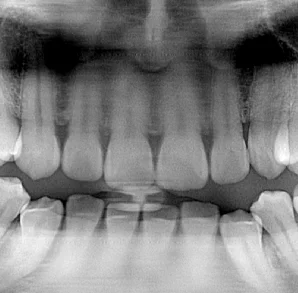

Luckily, because the panoramic x-ray performing the scan has the ability to capture many focal troughs, the operator can choose from any of the other panoramic images that were captured in that scan. Very quickly, the operator can select the image that reveals #8 and #9. This image is from the same panoramic scan as the one above. Same patient. Same scan.